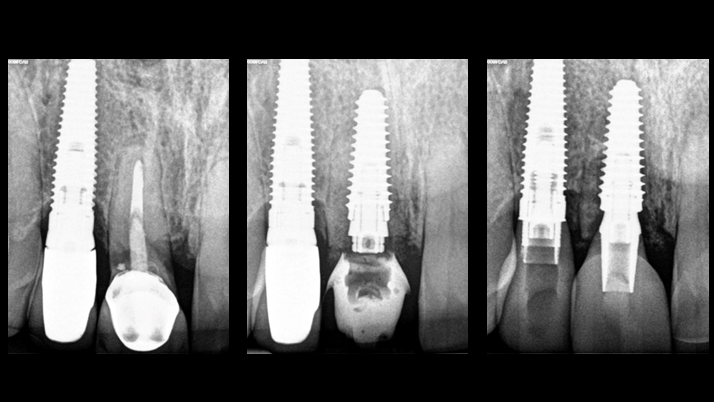

Clinical case: BPET PREDICTABILITY - State-of-the-Art SOCKET SHIELD

- Courtesy of Dr. Howard Gluckman, South Africa -

“AnyRidge is perfect for the anterior esthetic zone due to its strong initial stability & fast osseointegration.

Plus, KnifeThread® ensures space maintenance when using the PET/Socket Shield/Root Membrane Technique, showing excellent bone growth.”